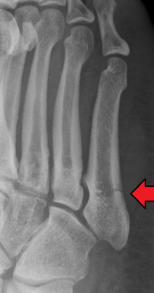

Jones fracture

Fracture to base of 5th metatarsal

Jones fracture signs/symptoms (3)

Pain, swelling/deformity, tender

Jones fracture treatment

PRICE, MD referral, surgery